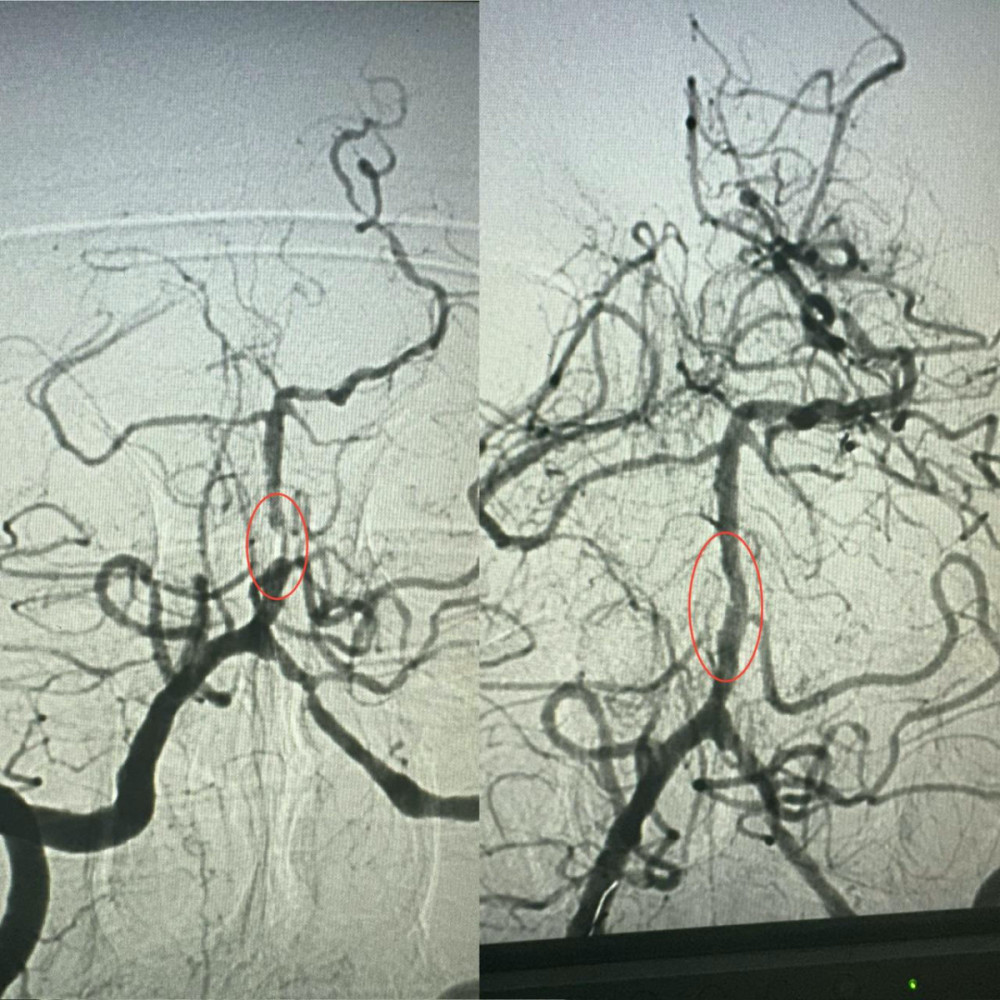

Завідувач рентгенендоваскулярного відділення лікарні Олександр Скрипка зазначив, що випадок був вкрай складним — ураження стовбура мозку. Базилярна артерія була майже повністю заблокована атеросклеротичною бляшкою, що робить такі інсульти одними з найнебезпечніших. Без термінової допомоги шанси на виживання вкрай малі.

Лікарі вирішили провести операцію з ангіопластики артерії. Хоча лікарня має досвід лікування атеросклерозу коронарних судин, застосування цієї методики для мозкових судин є інноваційним досягненням в Україні.

Операція тривала близько години. Сужену артерію розширили за допомогою спеціального балона, після чого використали балон з лікарським покриттям.